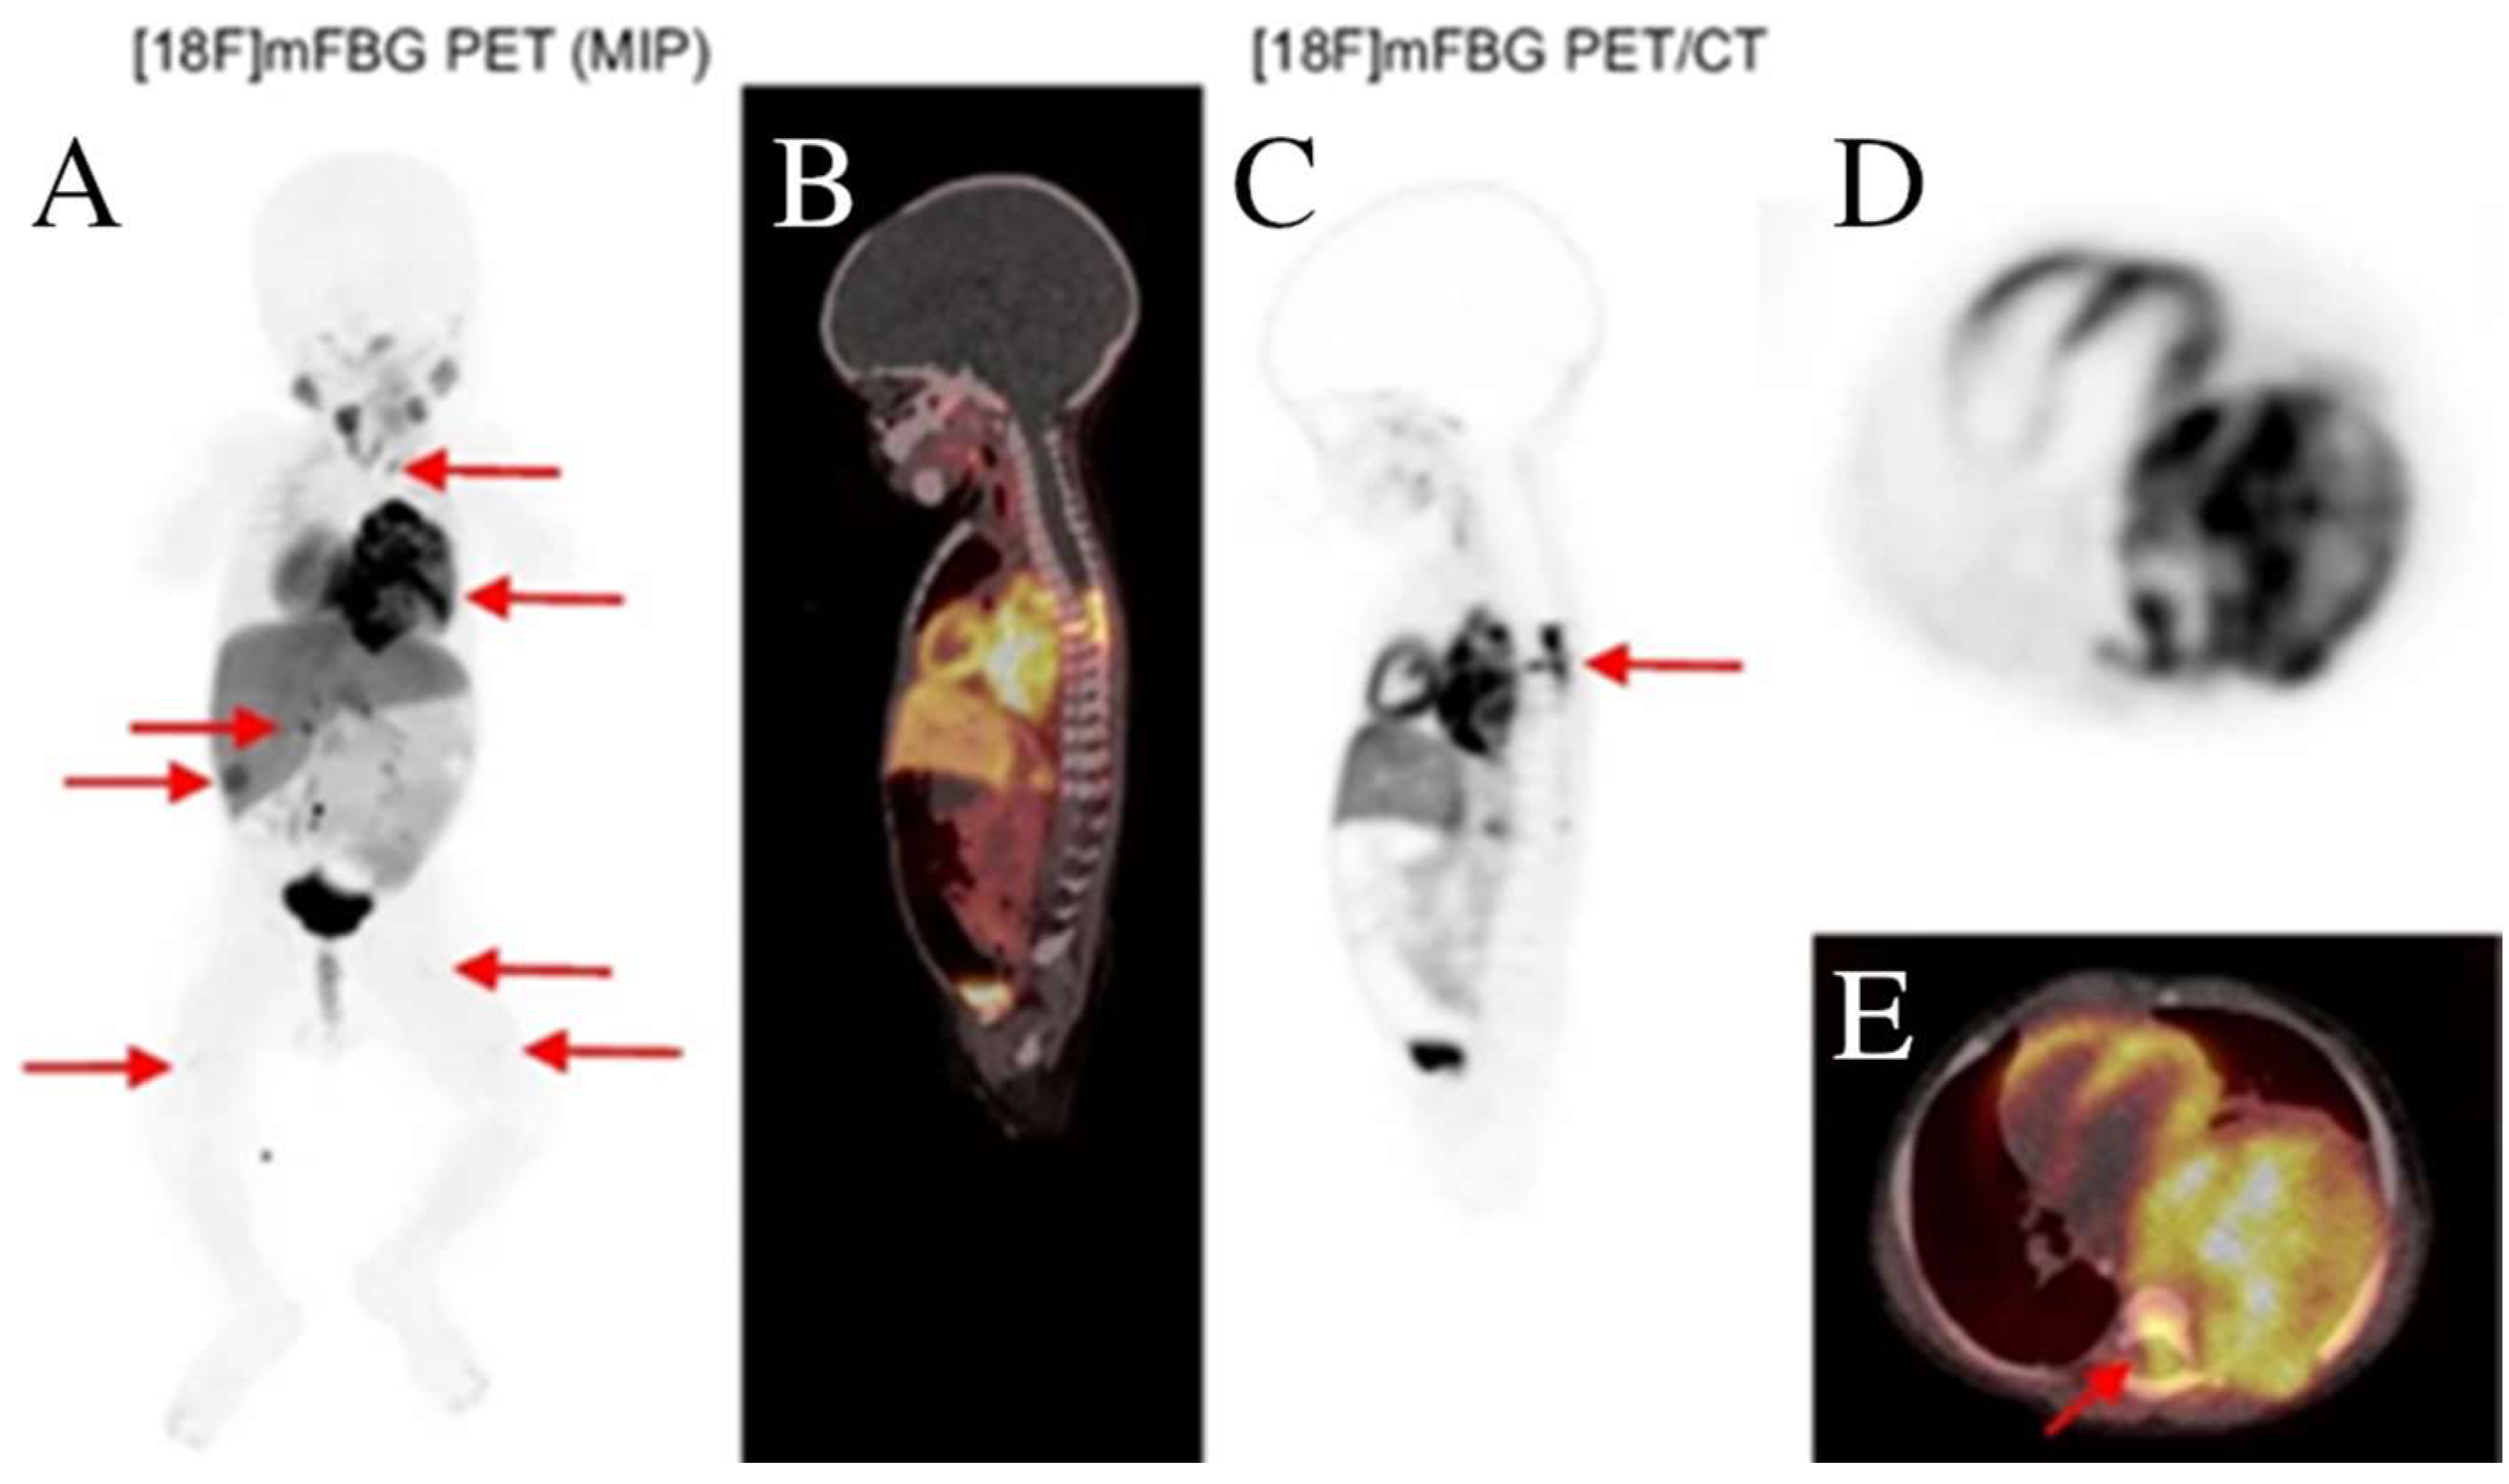

- Borgwardt, L.; Brok, J.S.; Andersen, K.F.; Madsen, J.; Gillings, N.; Fosbøl, M.Ø.; Denholt, C.L.; Wehner, P.S.; Enevoldsen, L.H.; Oturai, P.; et al. [18F]mFBG long axial field of view PET-CT without general anaesthesia reveals concise extension of neuroblastoma in a 9-month-old boy. Eur. J. Nucl. Med. Mol. Imaging 2023, 50, 2563–2564. [Google Scholar] [CrossRef]